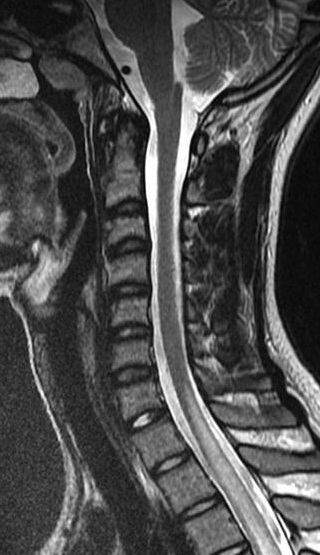

A MRI scan of brain and spine showed increased T2 signal and expansion of the cord in some areas of the spinal cord at the levels of C2–C5, and C7 to T12. The patient was given methylprednisolone 1 gram intravenous for a period of 5 days and oral steroids for 4 weeks. Thyroid function tests were reported to be normal (Table 3 [Tab. 3]). The patient showed marginal improvement in vision and reduction of sensory abnormalities by about 50% over a period of 6 weeks. In April 2015, the patient was admitted with cough associated with mucopurulent expectoration, shortness of breath, paraesthesias and diminished vision. The patient showed minimal improvement in sensory symptoms or vision. In May 2015, the patient was admitted with progression of bilateral lower limb weakness, bilateral upper limb weakness (distal > proximal) and a band-like sensation around the chest, syncope, vomiting and hiccups. Clinical examination revealed normal higher mental functions with diminished vision to finger counting in the right eye. Other cranial nerves were normal.

Immunological tests for ANA titer were 1:320, tests for anti-ENA, anti-dsDNA, anti-cardiolipin, anti-β2GPI, lupus cells, antibodies to GAD65, IA-2, insulin and cryoglobulins were negative. MRI brain and whole spine revealed 1) hyperintensity in cervical cord C5 to C7 level (Figure 1 [Fig. 1], Figure 2 [Fig. 2], Figure 3 [Fig. 3]); 2) hyperintensity in the thoracic cord till T12 level (Figure 4 [Fig. 4], Figure 5 [Fig. 5], Figure 6 [Fig. 6]); 3) hyperintensity in the right optic nerve head (Figure 7 [Fig. 7]). The clinical features and investigations (NMO IgG was positive) fit into the criteria of neuromyelitis optica. The thyroid profile was suggestive of hypothyroidism (Table 3 [Tab. 3]). Laboratory studies confirmed the presence of antithyroid antibodies (Table 4 [Tab. 4]). Fine needle aspiration of the thyroid showed lymphocytic infiltration of the thyroid gland (Figure 8 [Fig. 8], Figure 9 [Fig. 9]). The patient was treated with prednisolone 1 g/day for 5 days and azathioprine (2.5–3 mg/kg/daily). The patient showed improvement in motor symptoms and sensory symptoms approximately by 60% after a period of 2 months of treatment. Patient was started on thyroxine 50 μg and later dosage was increased to 100 μg.

Figure 2: MRI spine showing hyperintensity in cervical cord C5 to C7 level (2)

Figure 3: MRI spine showing hyperintensity in cervical cord C5 to C7 level (3)